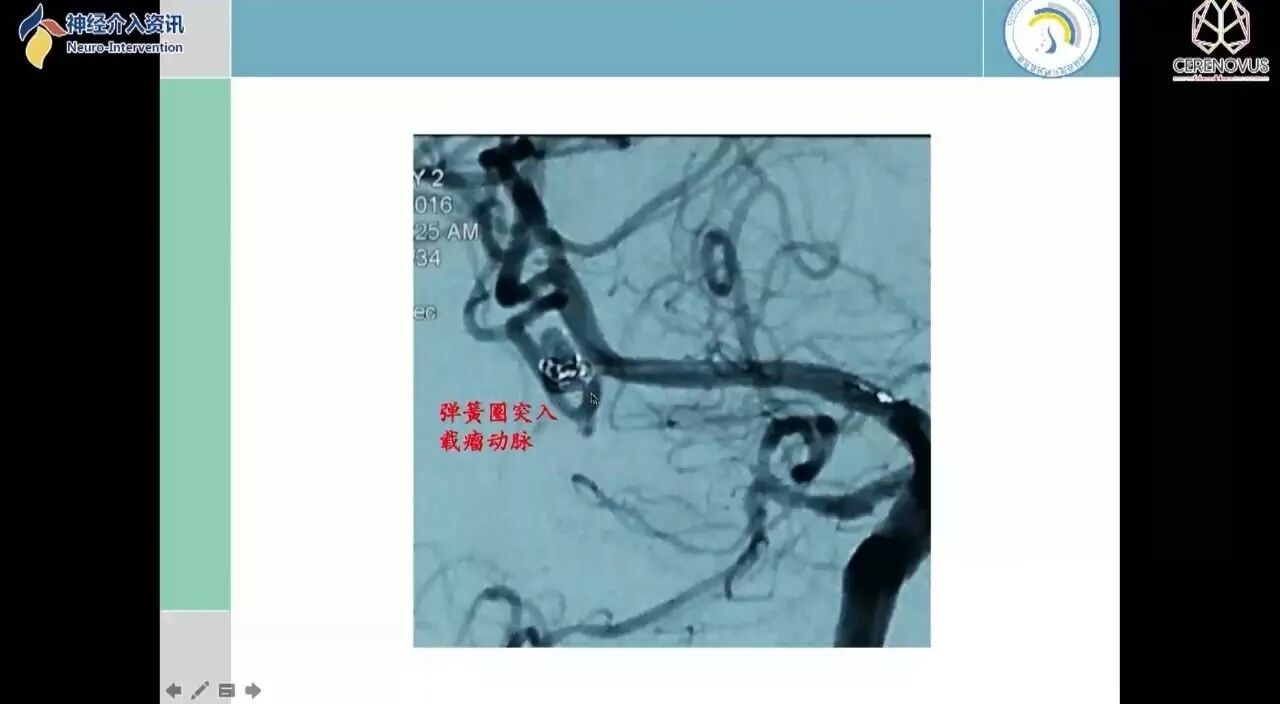

Galaxy弹簧圈在小动脉瘤栓塞术中的应用